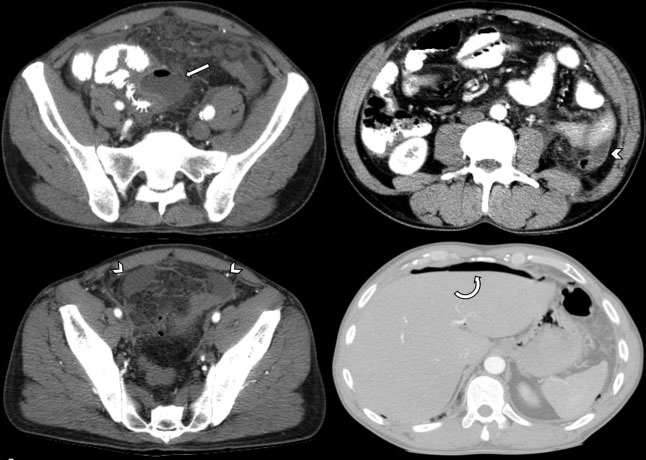

Con el objetivo de instaurar una correlación entre la clínica, los hallazgos tomográficos y el abordaje terapéutico, estableciendo el grado de severidad del cuadro con una visión multidisciplinaria, en 2015 Sartelli y col.12 propusieron una nueva clasificación y algoritmo de tratamiento (►Fig. 2), la cual será expuesta a continuación.12

Estadio 0: Divertículos con engrosamiento parietal del colon y aumento de la densidad de la grasa pericólica. Si el paciente se encuentra en buen estado general, se recomienda el tratamiento ambulatorio con o sin antibióticos; en caso de presentar signos de sepsis o comorbilidades, hospitalización con administración de antibióticos por vía oral o intravenosa (►Fig. 3).

Estadio IIA: Absceso > 4 cm (sin aire libre distante). Se recomienda drenaje percutáneo guiado por imágenes (►Figs. 5 y 6).